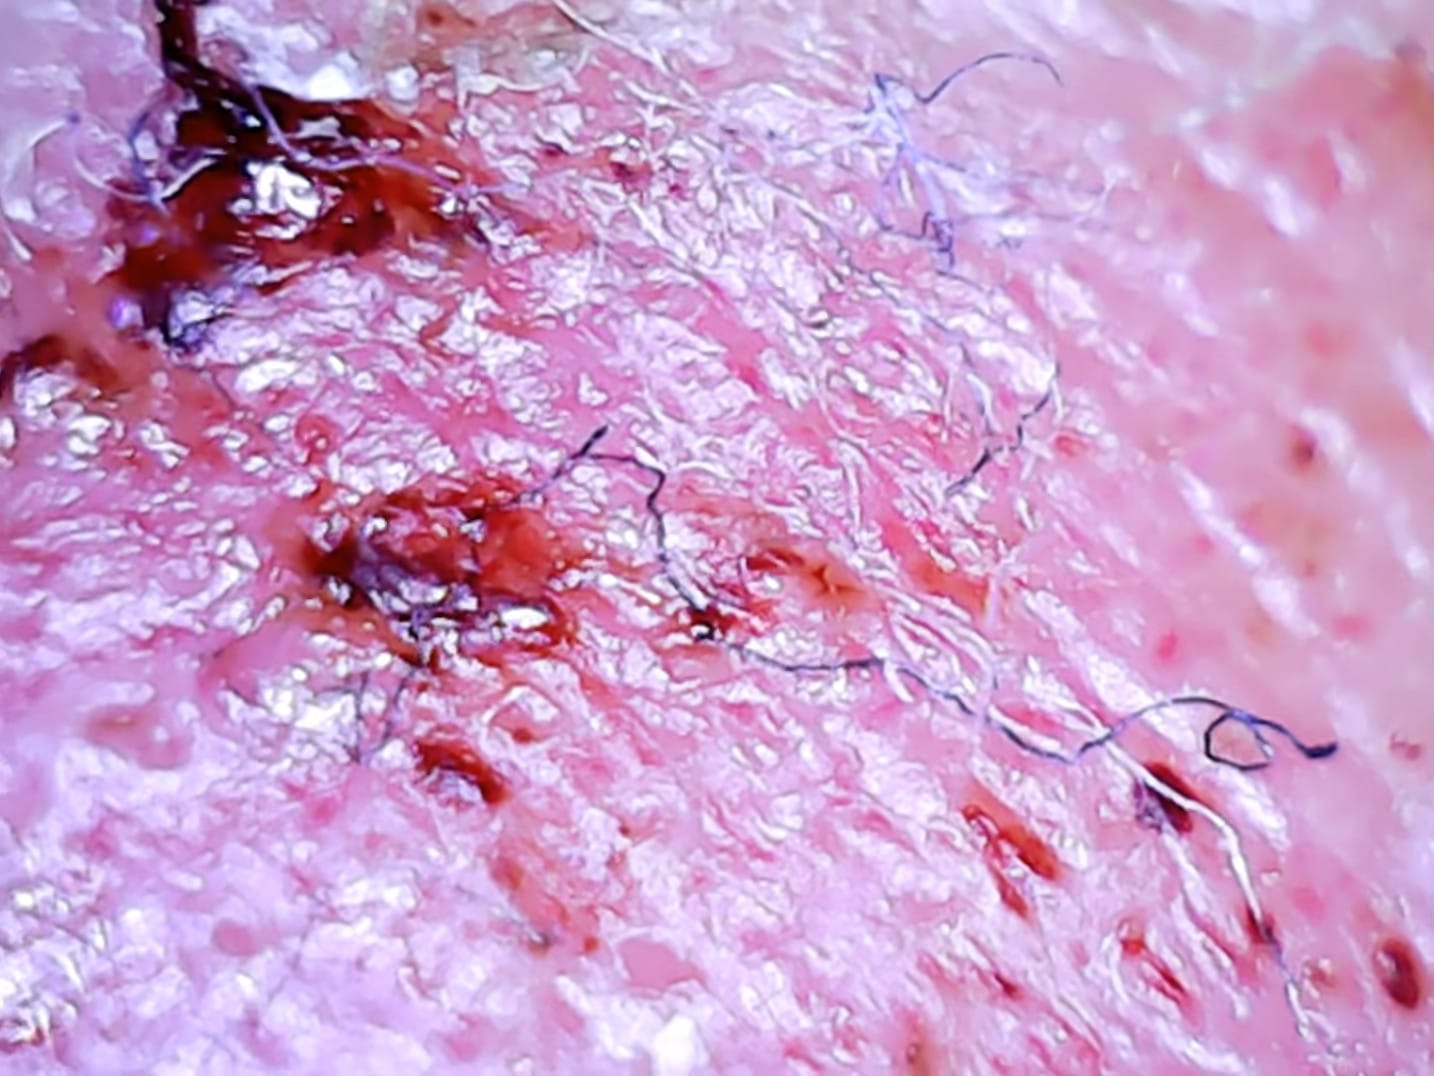

New Morgellons case-report. In this report a 45-year-old man presented to the emergency room after overdosing on Benadryl. The man was complaining about burning, and little barbs that appeared in his skin as worms or cocoons which he could express (expel). The physician thought the man may have Morgellons and referred him to psychiatry. Psychiatry … Read more